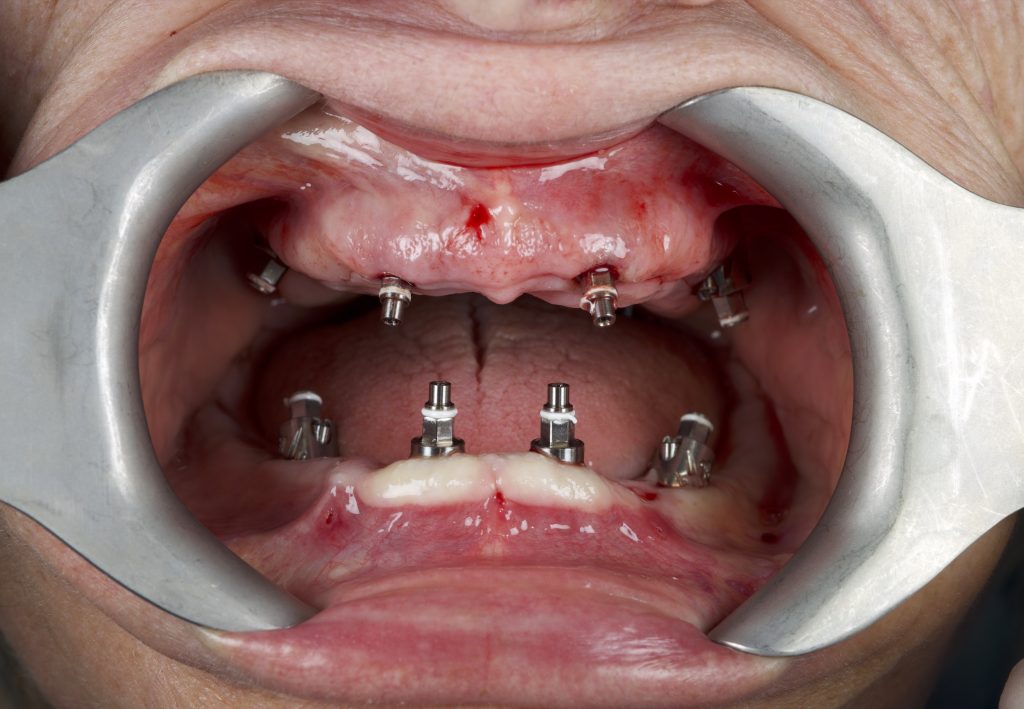

Previa anestesia locale con articaina 1:100.000, è stata fissata la dima guidata con frese di preparazione per i tre pin di fissaggio. Quindi, seguendo in sequenza le frese così come indicato per ogni sito implantare, sono stati inseriti i sei impianti mono-componente con MUA integrato B&B Dental con un torque d’inserzione di 35 N/cm. È stata eseguita una ops di controllo (Figure 8-13).

Al termine dell'inserimento implantare vengono smontati i connettori necessari per inserire lo specifico tipo di impianto e avvitati i marker sul MUA integrato per acquisire l’impronta intraorale, poi inviata con dati stl al tecnico (Figura 14).